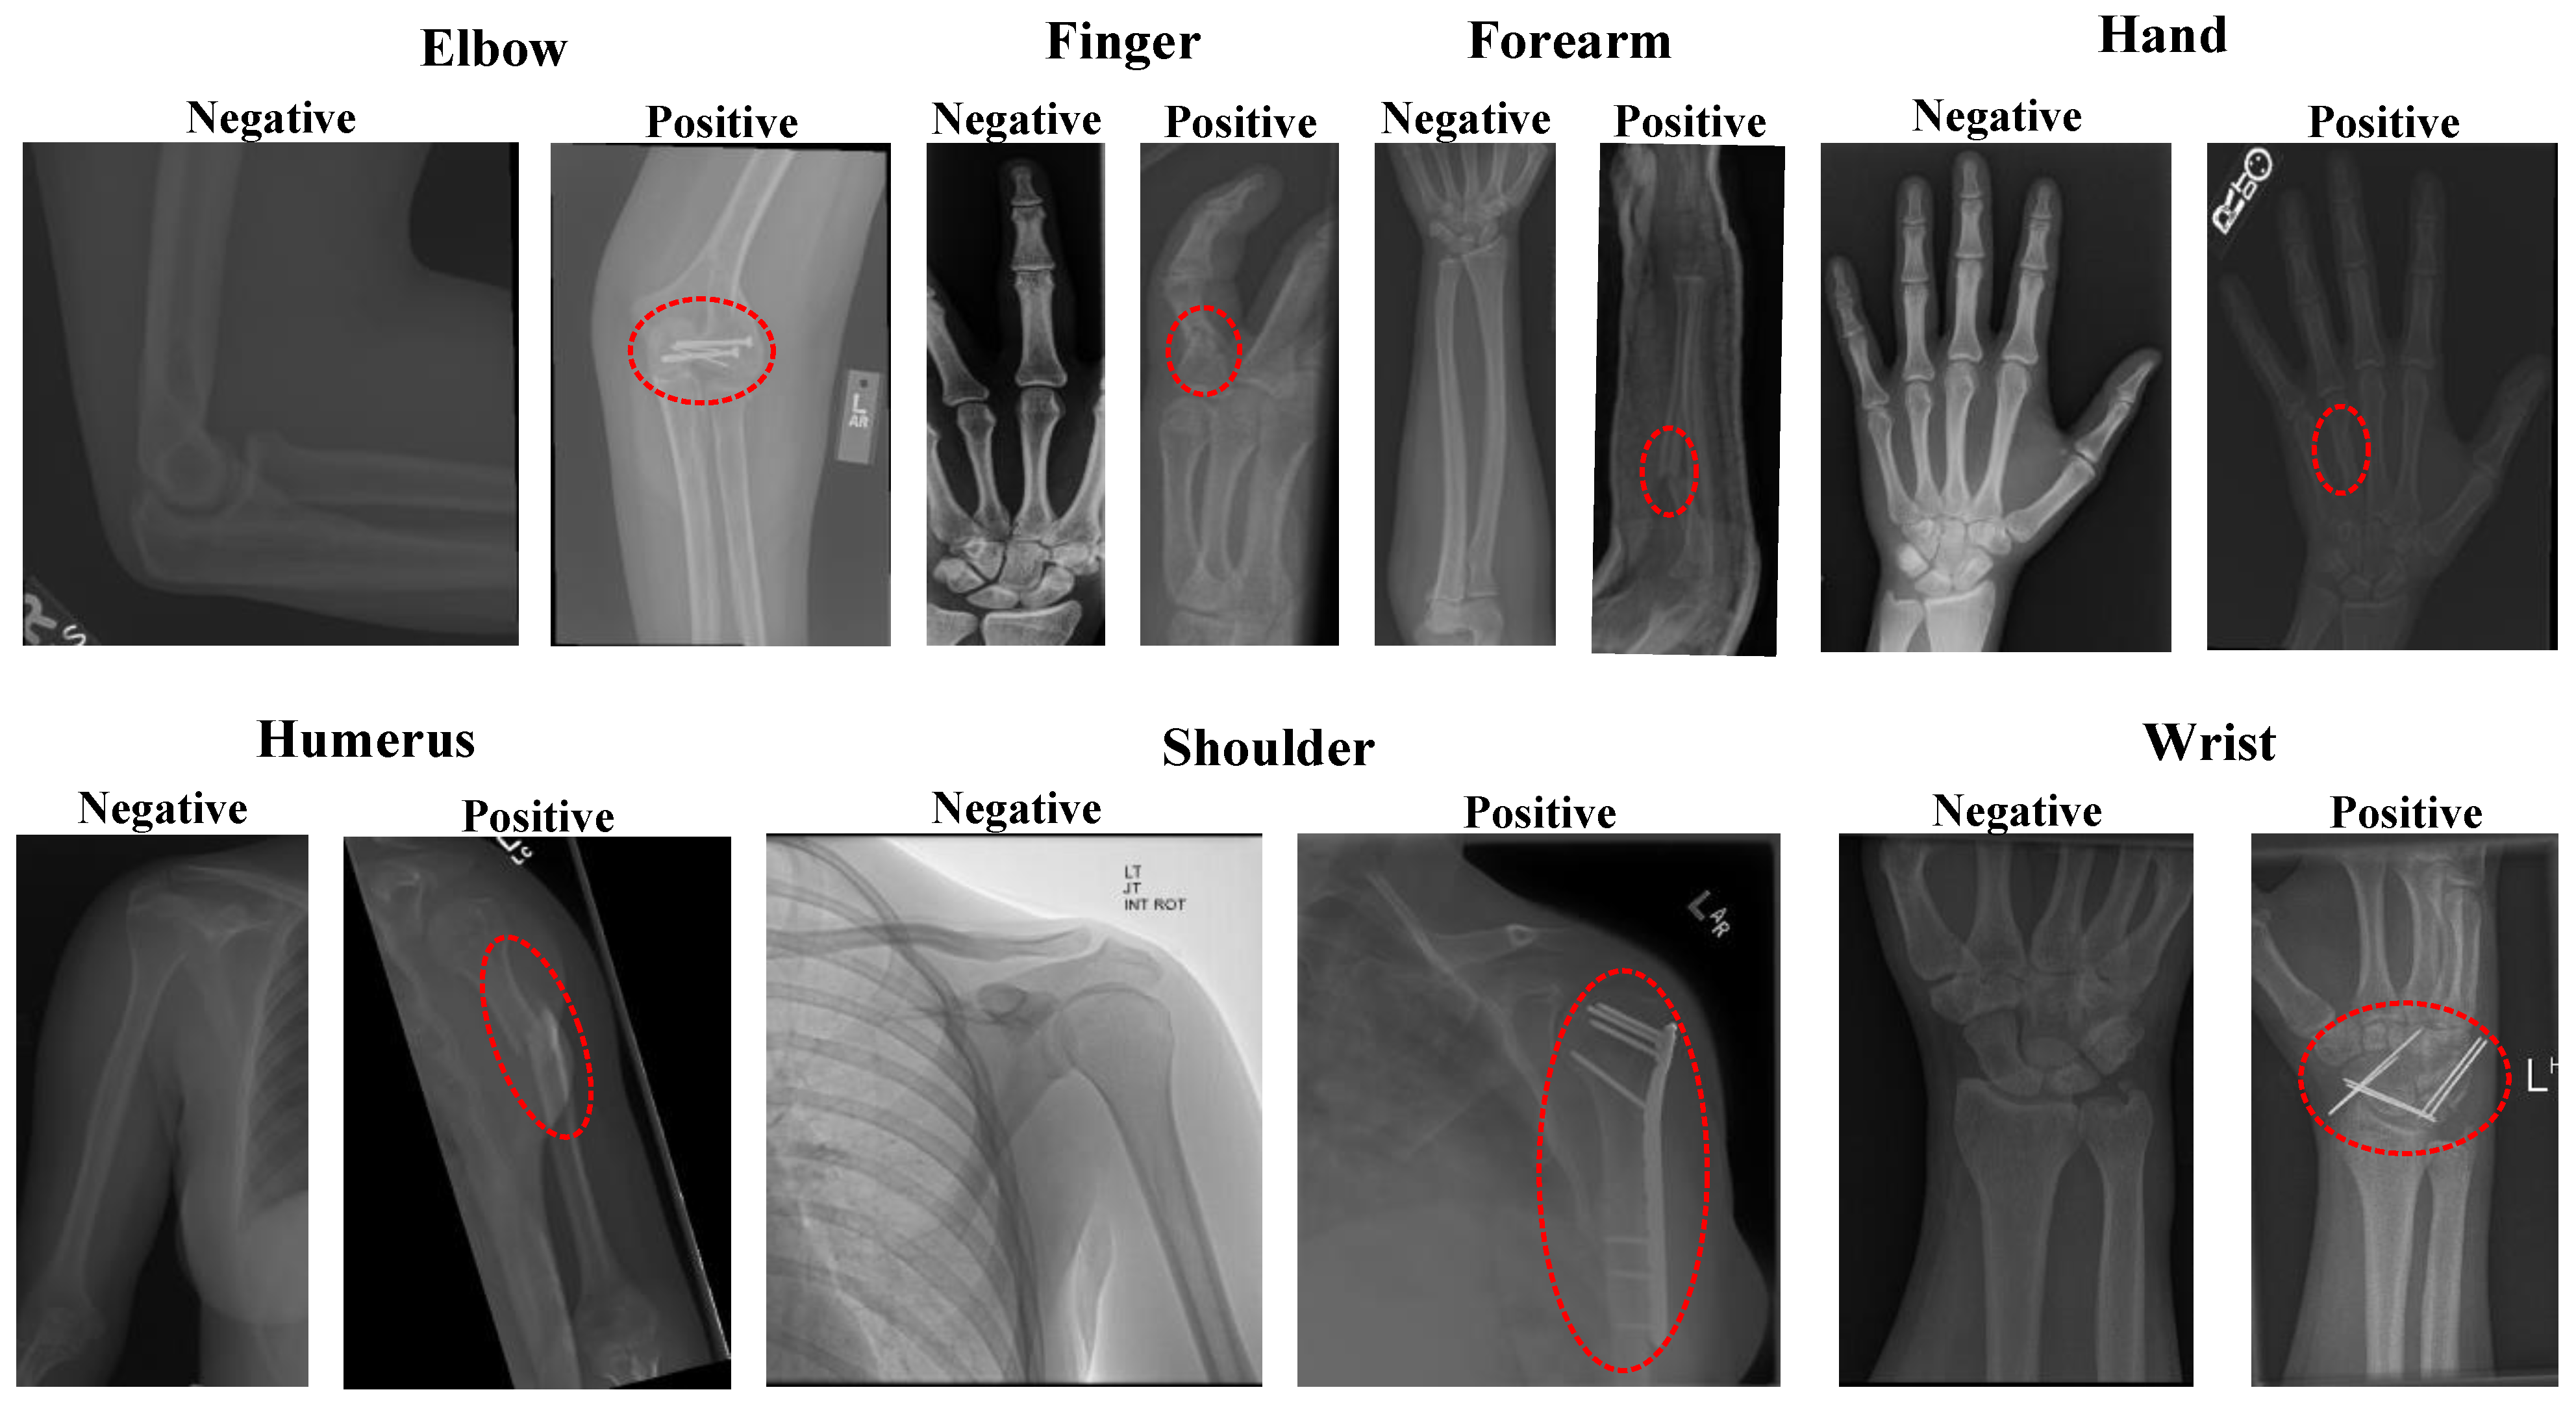

2.1. Dataset

| Classes | Accuracy (%) | Specificity (%) | F1-Score (%) | Recall (%) | Precision (%) | |

|---|---|---|---|---|---|---|

| Elbow | Negative | 92.04 | 86.18 | 93.45 | 96.10 | 90.94 |

| Positive | 96.10 | 89.86 | 86.18 | 93.87 | ||

| Finger | Negative | 91.19 | 87.45 | 92.88 | 93.53 | 92.24 |

| Positive | 93.53 | 88.44 | 87.45 | 89.45 | ||

| Forearm | Negative | 92.11 | 84.57 | 93.97 | 96.39 | 91.67 |

| Positive | 96.39 | 88.59 | 84.57 | 93.01 | ||

| Hand | Negative | 91.34 | 76.28 | 94.25 | 96.85 | 91.78 |

| Positive | 96.85 | 82.51 | 76.28 | 89.84 | ||

| Humerus | Negative | 91.35 | 88.15 | 92.02 | 94.21 | 89.93 |

| Positive | 94.21 | 90.57 | 88.15 | 93.12 | ||

| Shoulder | Negative | 89.49 | 87.81 | 89.70 | 91.14 | 88.31 |

| Positive | 91.14 | 89.26 | 87.81 | 90.75 | ||

| Wrist | Negative | 92.63 | 88.74 | 93.86 | 95.32 | 92.45 |

| Positive | 95.32 | 90.78 | 88.74 | 92.91 | ||